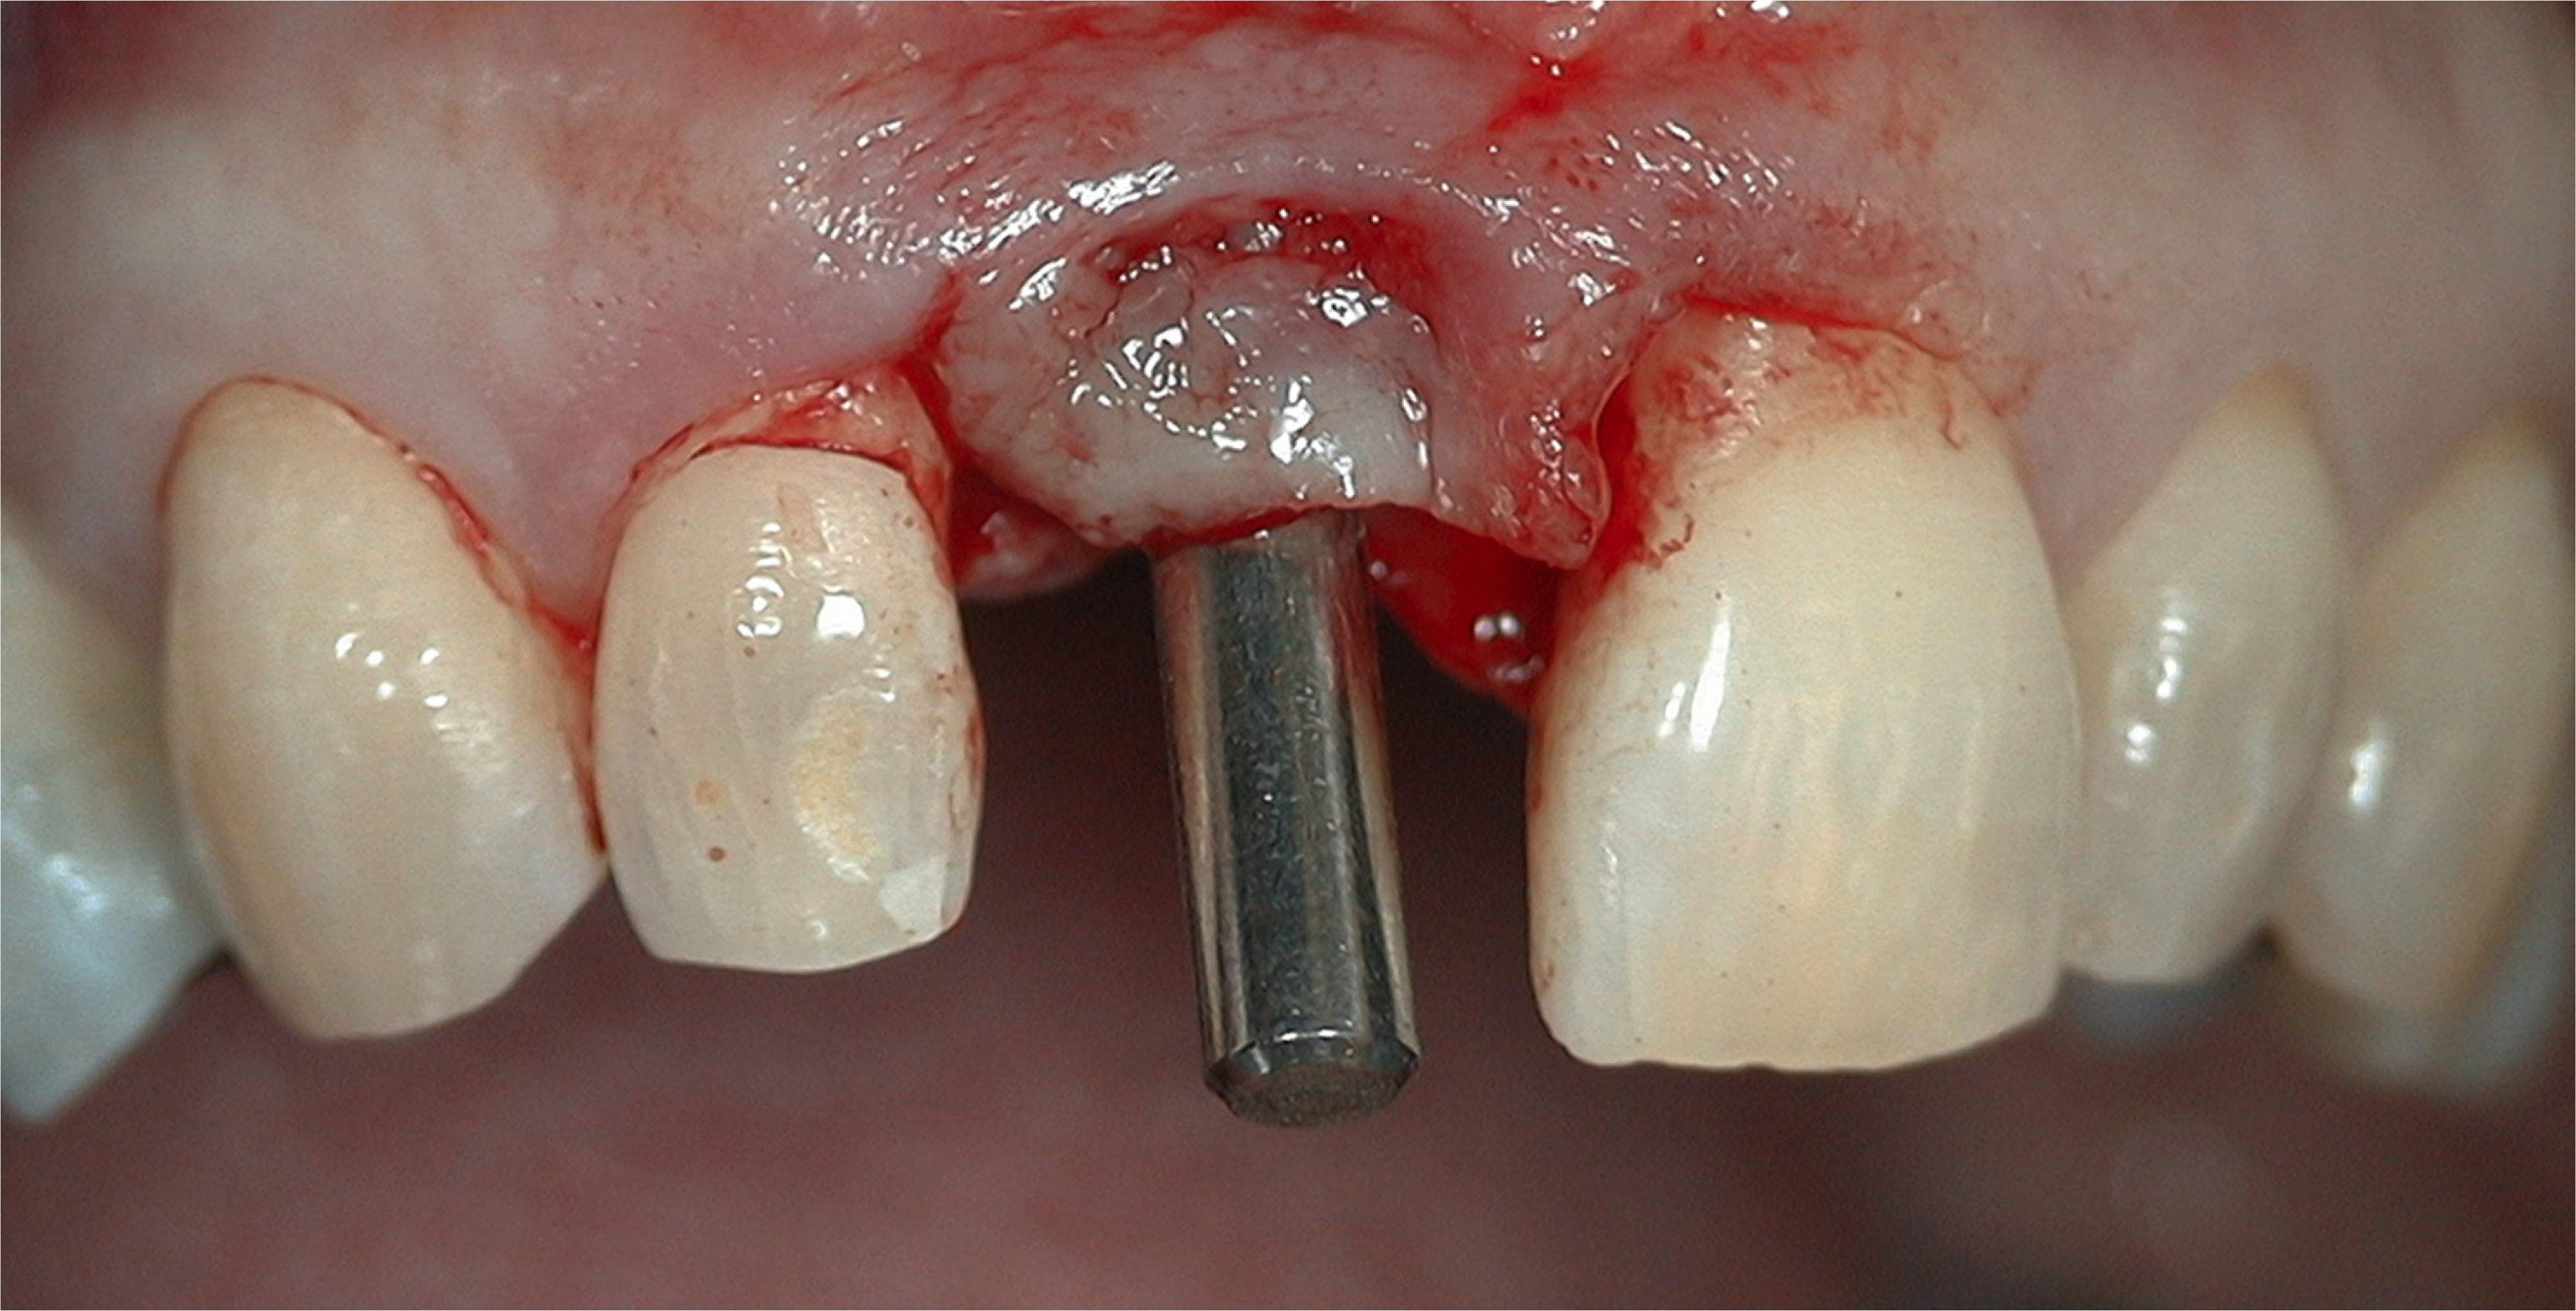

A flap procedure reveals the bone, which should be wide enough to provide 1.5 mm of bone on either side of the implant (Figure 5).6 The amount and level of bone surrounding implants is important for osseointegration, esthetics, and long-term survival.6 The location for implant placement can then be established using a round bur to place a mark in the center of the crest of bone from mesial-distally and facial-palatally (Figure 6).

Fig 5. 1.5 mm of bone should surround the implant on either side.

Figure 5

Fig 6. The location for implant placement can then be established using a round bur.

Figure 6